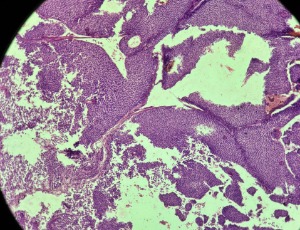

Surgical Approach to Pemphigus Vulgaris in the Lacrimal Punctum: A Case Report

Pemphigus comprises a rare but potentially life-threatening group of autoimmune bullous dermatoses that primarily affect the skin and mucous membranes. Histopathologically, it is characterized by the presence of intraepidermal acantholysis and deposition of IgG autoantibodies against desmosomal cadherins, notably desmoglein 1 (Dsg1) and desmoglein 3 (Dsg3), leading to compromised intercellular adhesion among keratinocytes.